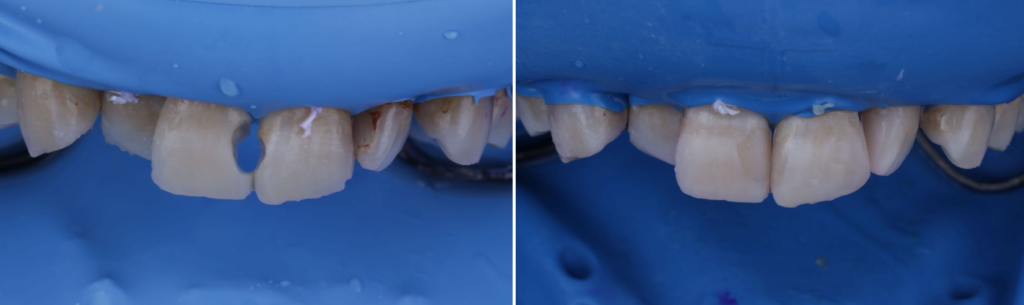

ダイレクトボンディングによる虫歯治療のメリット

「できるだけ歯を削らず、きれいに、長持ちする虫歯治療を受けたい」そんな方に今、選ばれているのがダイレクトボンディングです。

そしてこの治療は、どこで受けるかによって結果が大きく変わる治療でもあります。

菊川駅前歯科では…